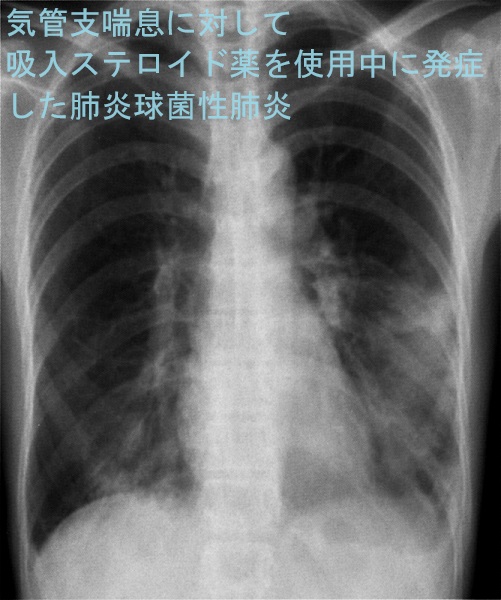

甲状腺と肺炎球菌

甲状腺機能亢進症/バセドウ病で甲状腺ホルモンが正常化していない時に肺炎球菌に感染すると、甲状腺クリーゼをおこし、生命に危険を及ぼす可能性があります。

また、甲状腺ホルモンが正常化していない甲状腺機能低下症/橋本病では肺炎球菌感染により粘液水腫性昏睡に至る可能性もあります。